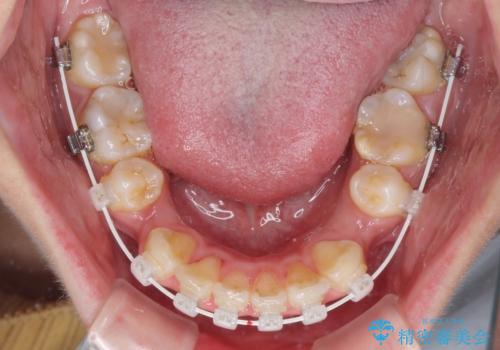

- 矯正装置

- 審美装置

4本の歯を抜歯したことで、飛び出していた口元が引っ込み、横顔が大きく改善されました。

咬み合わせが悪化することのないようにスペースを閉じていくことができ、比較的スムーズに治療を進めることができました。